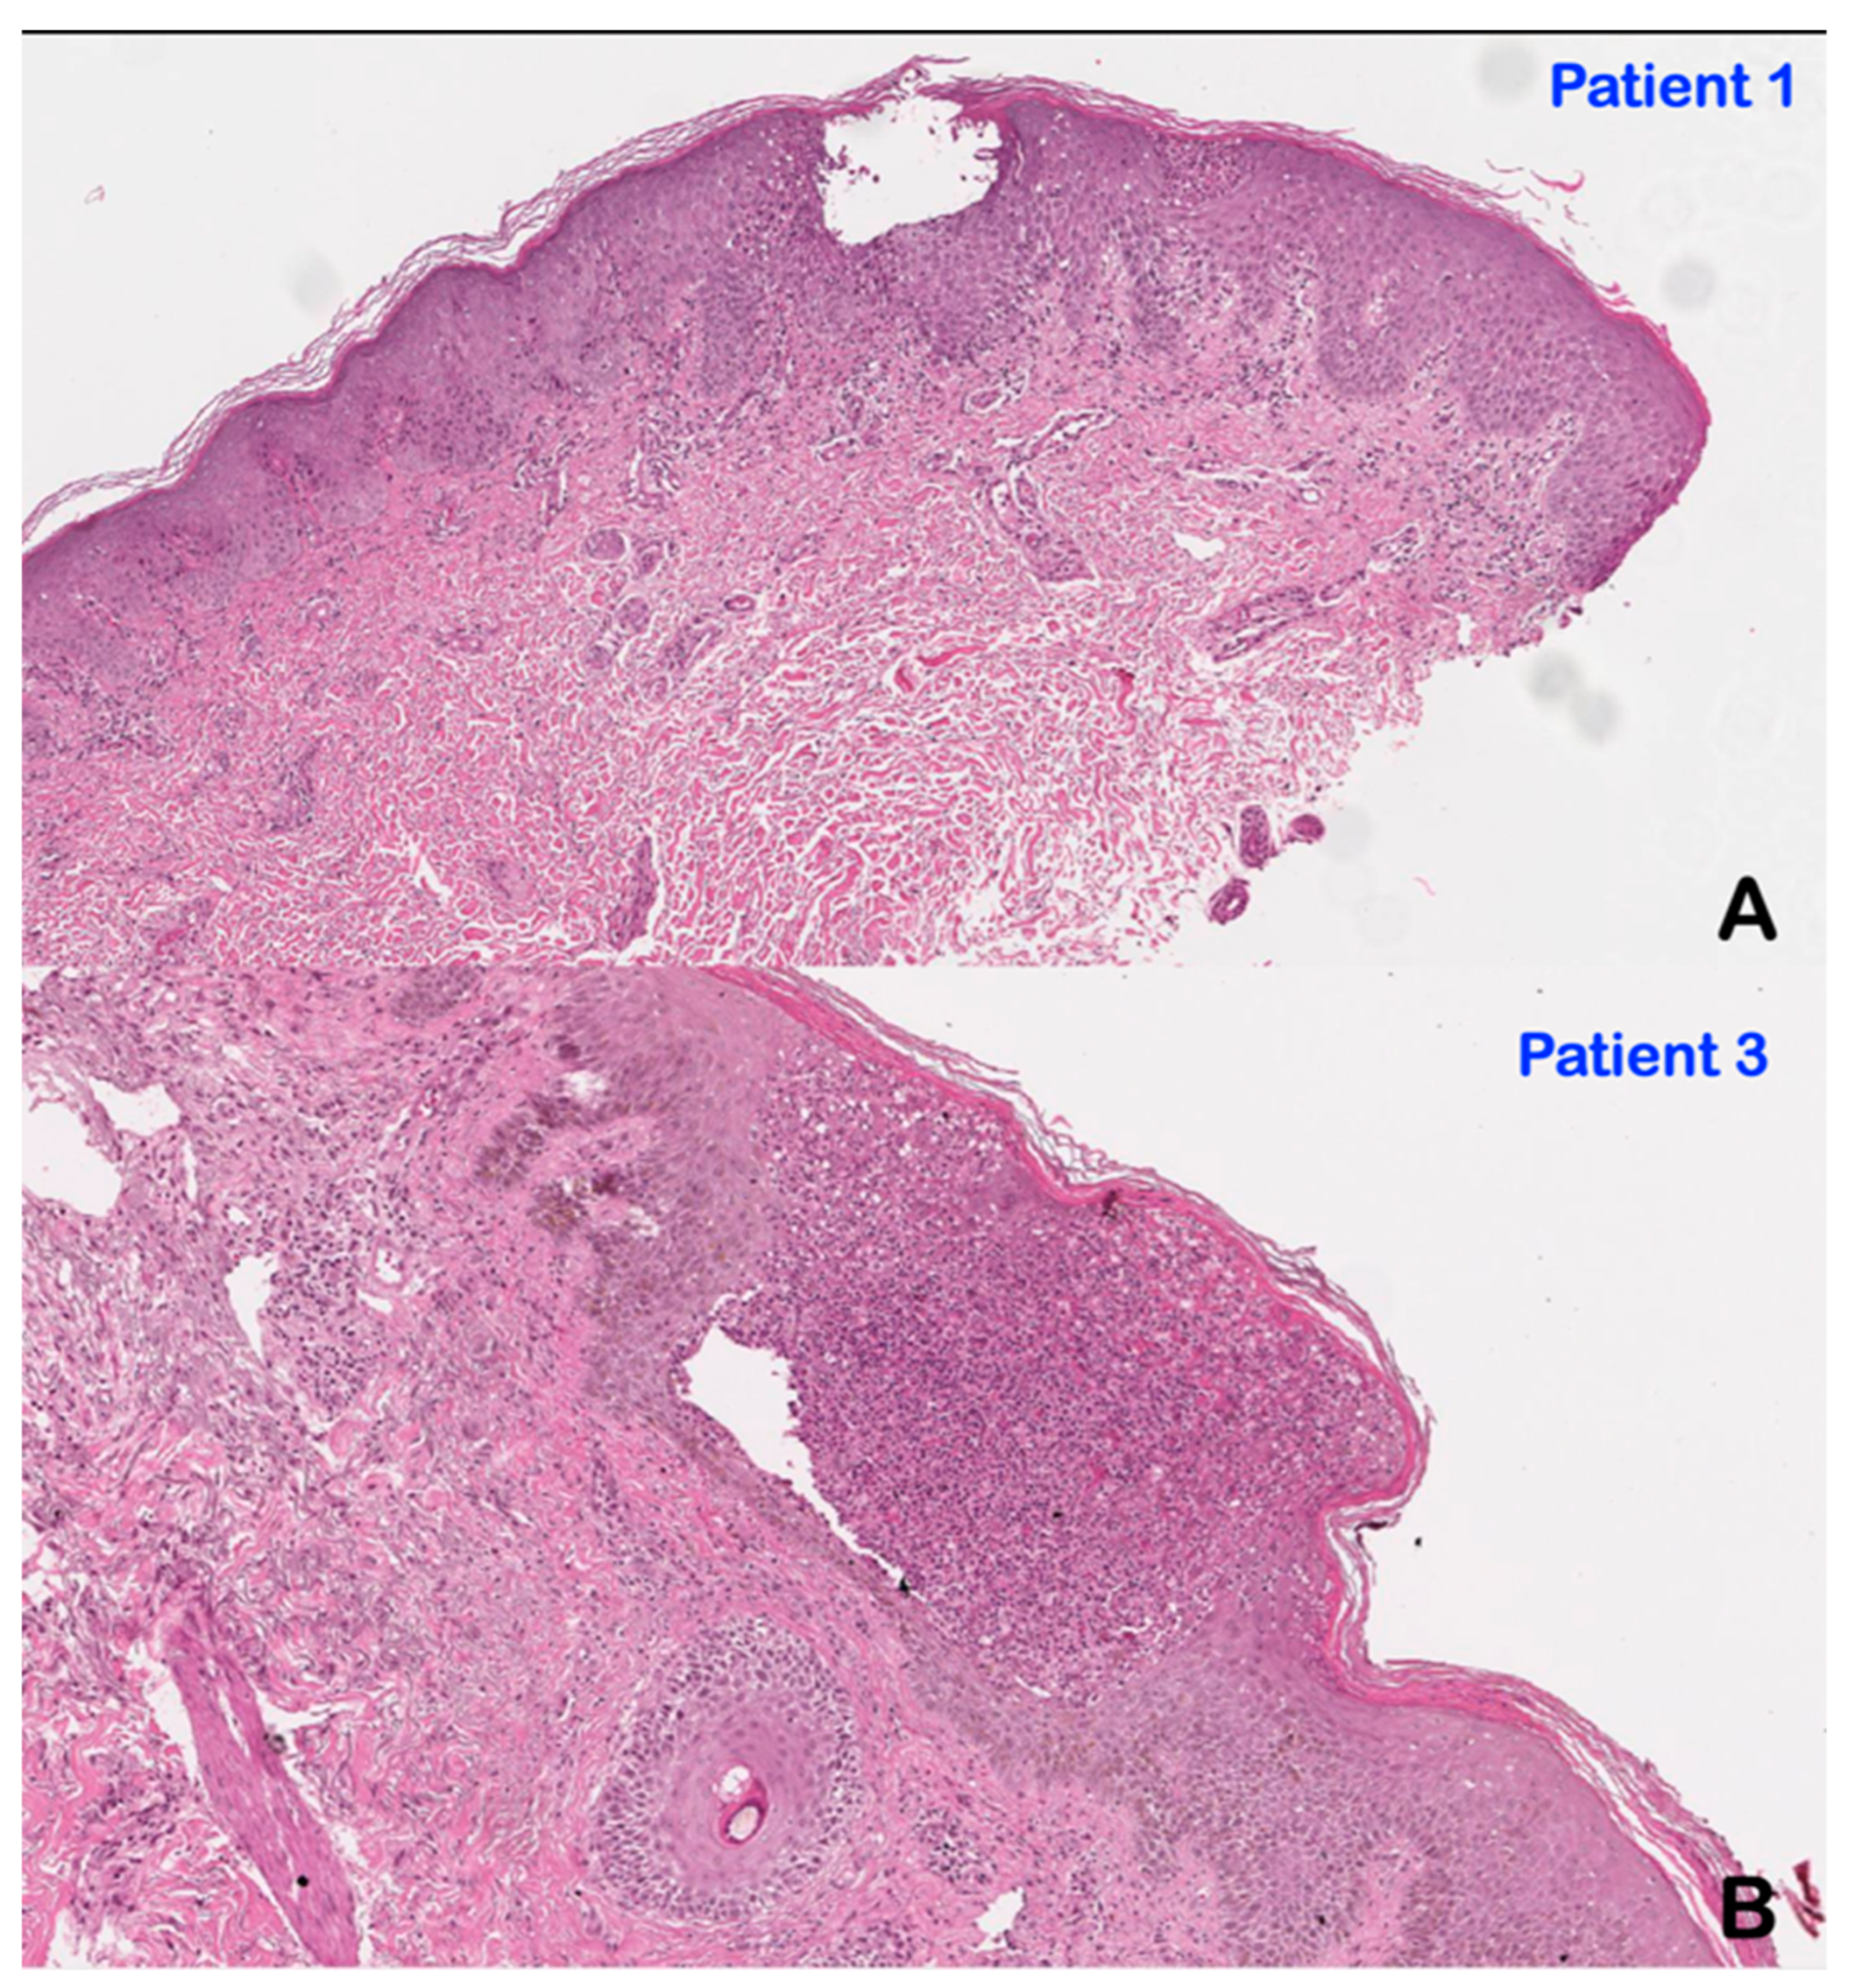

3.2. Histopathological Findings